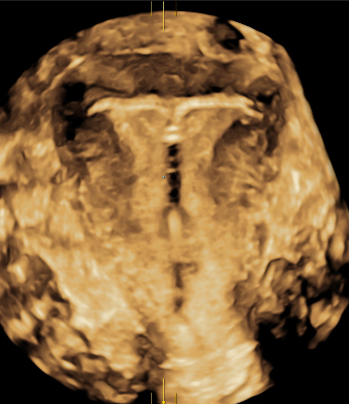

A detailed ultrasound assessment of your uterus and ovaries. This can be performed transabdominally (through your tummy with a full bladder) and/or transvaginally (with your consent) for a high-resolution, detailed assessment of the uterus, ovaries and surrounding structures.Transabdominal assessment through full bladder

Transvaginal assessment (with consent) for detailed imaging

Assessment of uterus, ovaries, and surrounding structures

Some of the reasons why we do a pelvic ultrasound include Post Menopausal Bleeding (PMB), Intra Uterine Contraceptive Device (IUCD/Mirena) positing, Polycystic Ovaries (PCOS) and Pelvic Pain, to name a few.